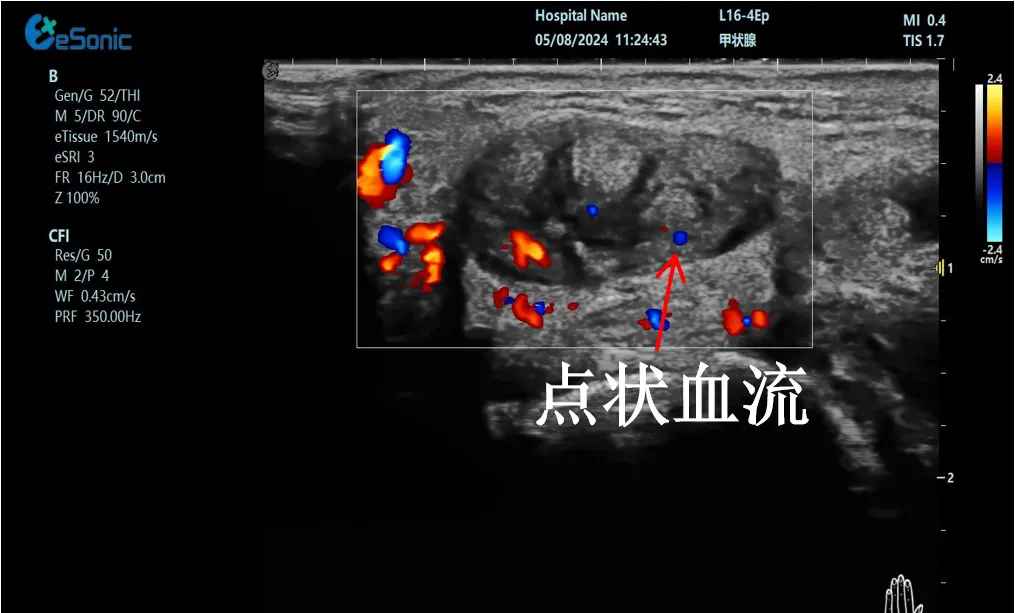

mFlow?技术在腱鞘炎诊疗中的应用

【背景】:左手腕关节第四腔室腱鞘炎。

【痛点】:普通彩色多普勒不敏感,只能看到细小点状血流,容易被忽略,难以进行分级诊断和疗效评估。

【方案】:银河官网医疗(ESI)超微血流技术可以看到腔室内肌腱周围环状血流,可充分提示:

1、处于炎症活动期;

2、根据血流进行分级诊断提示1级;

3、治疗后根据血流多少评估疗效(见右下图:治疗10天后复查超声,微血流图像血供消失)。